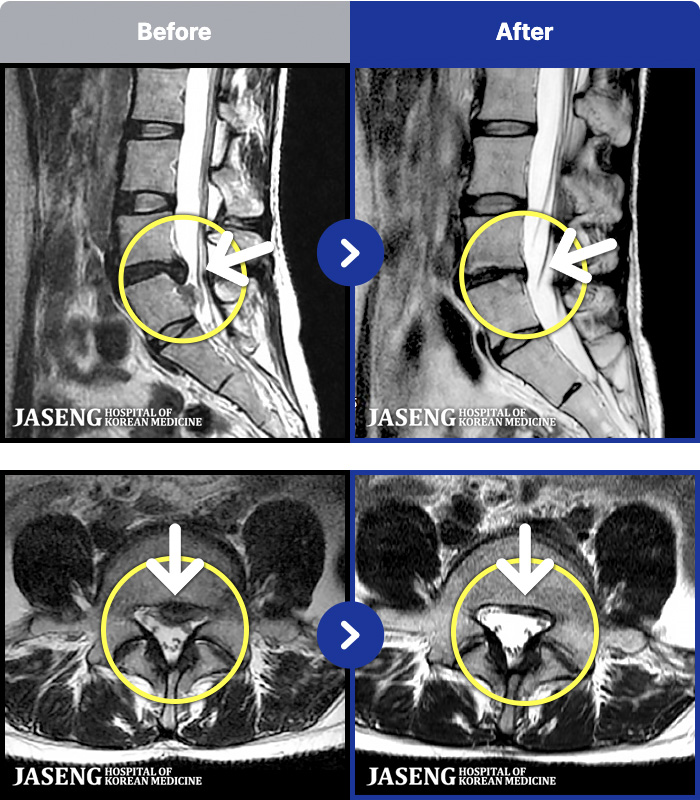

- MRI ġ

MRI ġ

181 MRI ũ ʸ Ȯϼ.